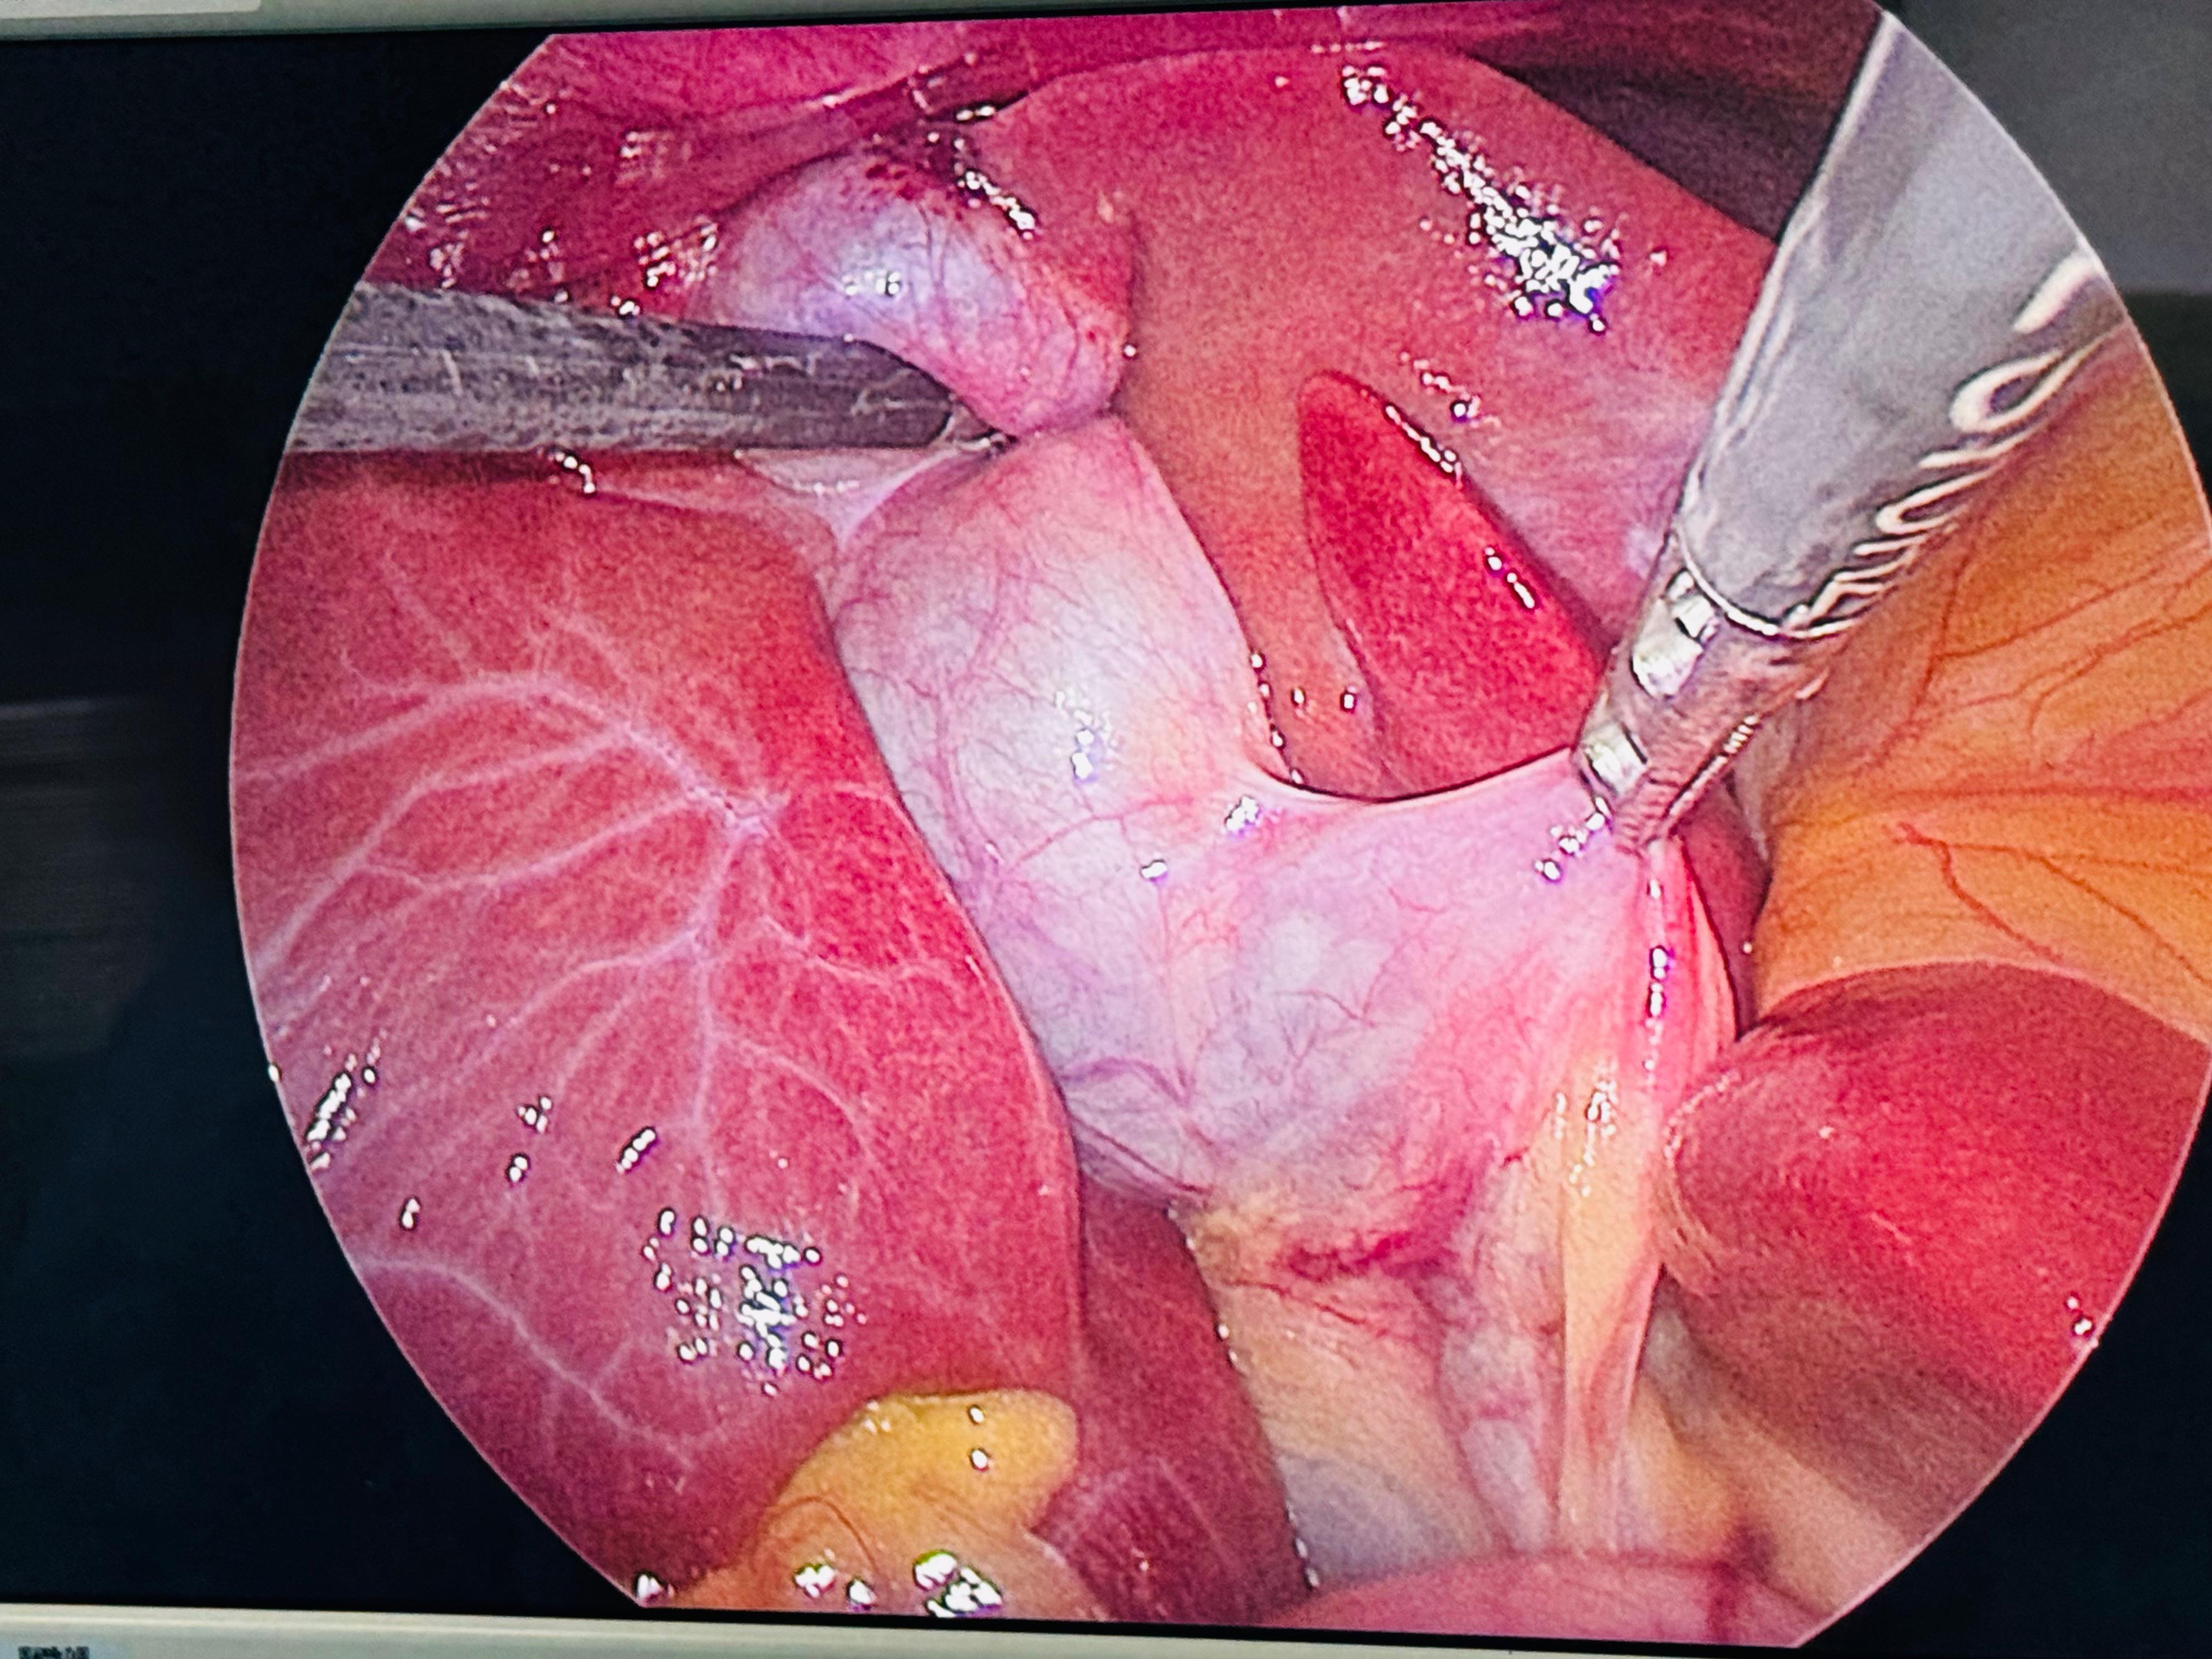

Dr Monika Joshi presented in the session on “Horrors of Laparoscopy” at the prestigious Indian Association of Gastrointestinal Endo-Surgeons (IAGES) ELSA – an international conference held at the elegant The Westin Mumbai Powai Lake.

Presenting on one of the most challenging and feared complications in minimally invasive surgery was both humbling and enriching. The session brought together experienced surgeons from across the globe, fostering meaningful discussions, shared learning, and surgical wisdom.